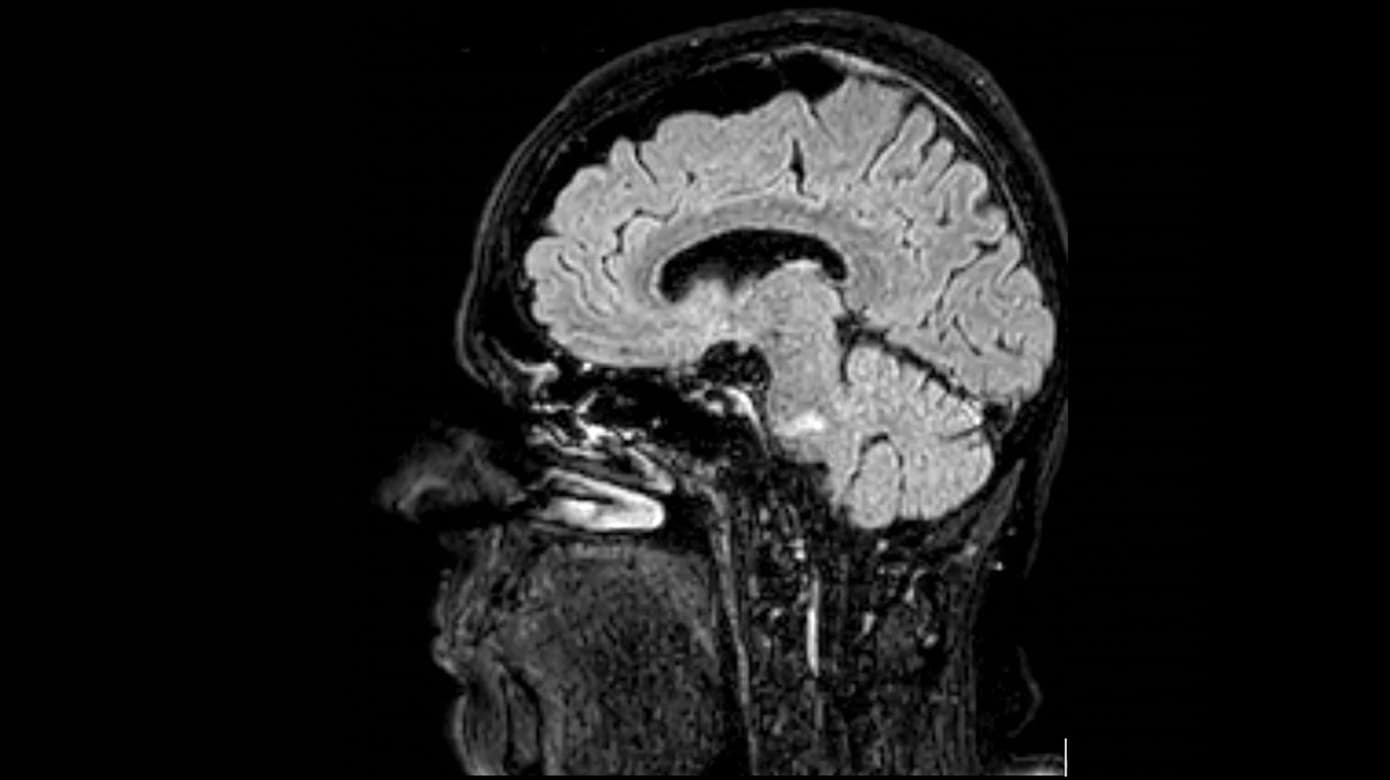

MR-skanning af cerebrum to dage efter debut viste et friskt venstresidigt pontint infarkt (Figur 1) foreneligt med patientens symptomer. UL-skanning af halskar viste forkalkninger bilateralt uden stenoser. Blodprøvescreening, ekg, telemetri, urinstiks og SARS-CoV-2-podning ved indlæggelse var upåfaldende. CT-angiografi blev ikke udført, da patienten hverken havde nakkesmerter, hovedpine, Horners syndrom eller fluktuerende symptomer.